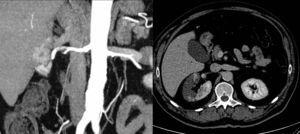

Given the patient’s intense pain and high LDH level, computed tomography was performed. The scan revealed an extensive right renal infarction with a filling defect in the main renal artery, proximal to its trifurcation (Figure 1).

Figure 1. Different computed tomography views of the right renal infarction